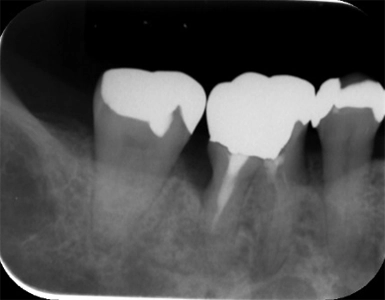

CASE1

歯周組織再生療法(保険診療)

術前

術後(1年後)

年齢・性別 50歳・女性

主訴 市の歯周病健診で歯周病を指摘された

診断名 広汎型慢性歯周炎ステージⅢグレードB

治療内容 歯周基本治療 歯石除去、ブラッシング指導により歯肉の炎症をできる限り改善し、その後歯周ポケットが深く歯槽骨の破壊が大きい部分に対して、歯周外科処置を行った。

治療期間 初診から歯周外科処置まで約5カ月、その後メインテナンス

費用 保険診療にて行う

リスク・副作用 術後の痛み、腫れ、出血が出ることがある

感染の可能性、腫れや再生不良が起こることがある

喫煙や清掃不良、炎症が重度の場合は組織再生の効果が十分得られないことがある

歯肉が引き締まる過程で知覚過敏が起こることがある。